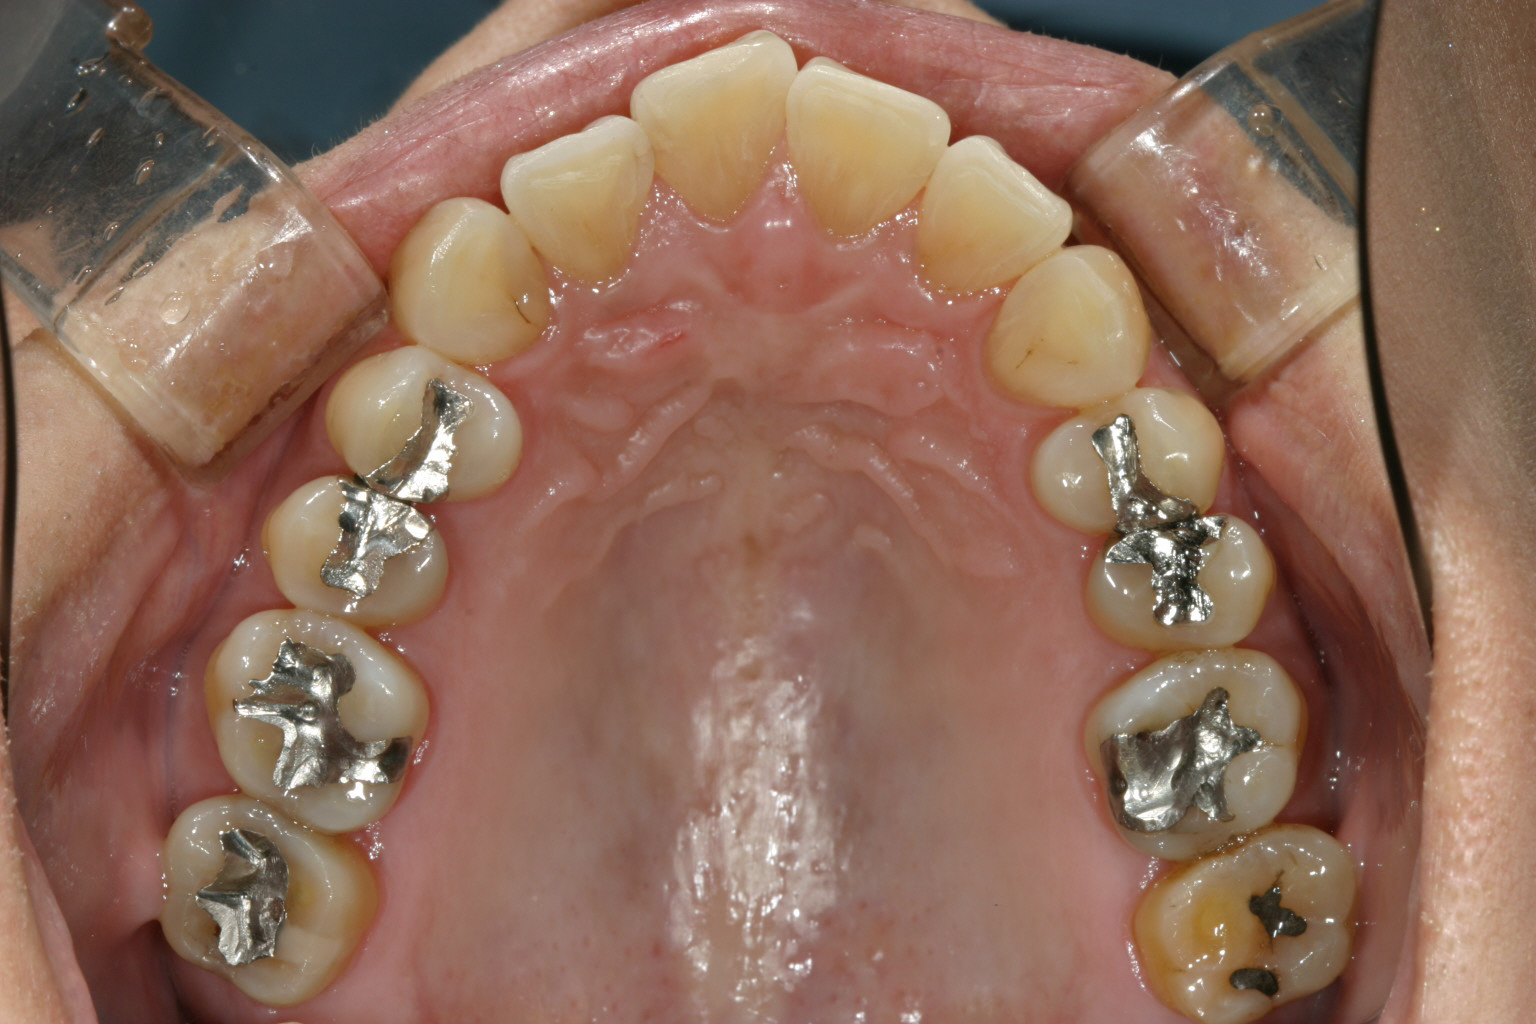

左右の臼歯部に高さの誤った冠が被っている為、後にこれを8本入れ替え正常な顎位に変更する。

上顎にマルチループワイヤーを入れアーチフォームを改善する。 アーチフォームもU字変更している。

下顎は8本の臼歯を仮歯に変更して顎位を修正したのちマルチループワイヤーにてかみ合わせの調整を行う。 最初右にも左と同様のプラスティックレジン冠を入れるが顎位が右に戻る傾向があり咬耗激しく現在の様な金属冠に変更する。(全体的に少し高さを挙げて特に右側を沢山挙げる事により顎位が左へシフトさせる) アーチフォームもU字変更している。